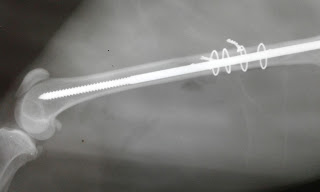

CIRUGÍA GENERAL Y DE TEJIDOS BLANDOS, TRAUMATOLOGÍA Y ORTOPEDIA, CARDIOLOGÍA, RAYOS X, ECOGRAFÍAS, LABORATORIO CLÍNICO....DR. MARCELO E. CANDO L. M.V.Z. -ESTAMOS UBICADOS AL SUR DE QUITO EN LAS CALLES HOPPE NORTON S-928 Y ADRIÀN NAVARRO, A UNA CUADRA DEL PATRONATO MUNICIPAL SAN JOSÈ. INFORMES AL 02-2648 115 -0984992384 ... QUITO-ECUADOR